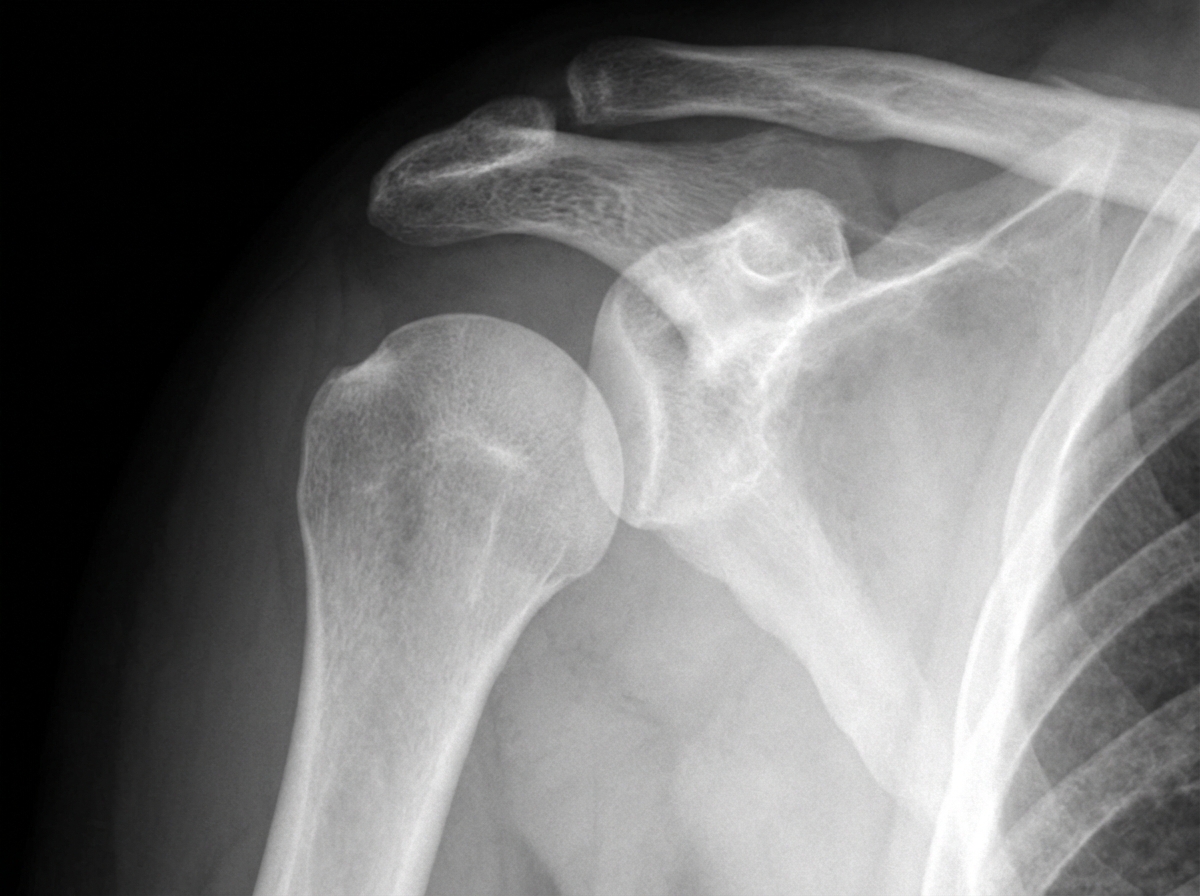

A 54-year-old male patient sustained a right upper limb injury in a road traffic accident and presented to the emergency room unable to move his right arm. Radiographic findings are shown. Which of the following nerves is most likely injured?

Explanation: ***Axillary nerve*** - **Anterior shoulder dislocation** or **surgical neck of humerus fracture** commonly injures the axillary nerve due to its anatomical course around the surgical neck. - Injury results in **deltoid muscle paralysis** (inability to abduct arm) and **loss of sensation** over the lateral shoulder (regimental badge area). *Radial nerve* - Most commonly injured with **midshaft humerus fractures** due to its spiral course in the radial groove. - Causes **wrist drop** (inability to extend wrist) and **weakness of finger extension**, not complete arm immobility. *Ulnar nerve* - Typically injured with **medial epicondyle fractures** or **elbow trauma** affecting the cubital tunnel. - Results in **claw hand deformity** and **weakness of intrinsic hand muscles**, preserving shoulder and arm movement. *Median nerve* - Commonly injured in **supracondylar fractures** of the humerus or **carpal tunnel syndrome**. - Causes **ape thumb deformity** and **thenar muscle weakness**, but does not affect shoulder or arm movement.